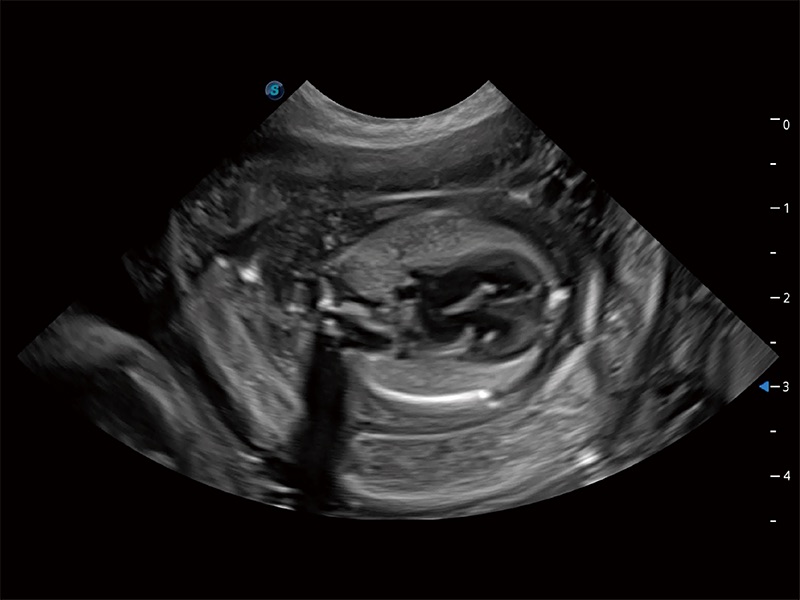

ProPet 80 全新的動(dòng)物超聲智能軟件和豐富的探頭群,為動(dòng)物醫(yī)生提供了高清晰度和精細(xì)分辨率的圖像,無(wú)論在寵物、馬科、畜牧還是實(shí)驗(yàn)室動(dòng)物等應(yīng)用中都可以輕松應(yīng)對(duì),為您的日常工作帶來(lái)滿意的體驗(yàn)。